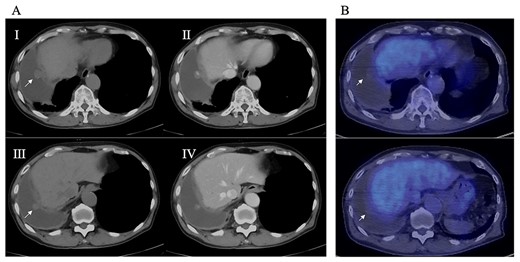

An 81-year-old man who underwent surgical resection for lung cancer 2 years previously was referred for the examination of a right diaphragmatic mass that was pointed out during follow-up. Computed tomography (CT) revealed pleural effusion and two contrast-enhanced nodules (17 × 10 and 10 × 10 mm) in the right diaphragm (Fig. 1A); however, he had no symptoms. Positron emission tomography (PET)/CT was performed, but no FDG accumulation was found (Fig. 1B). Although hemangioma was suspected based on the preoperative imaging, we were unable to exclude the recurrence of lung cancer. Therefore, the patient was admitted for the examination of the right diaphragmatic nodules by VATS. A 4-cm thoracotomy wound was created at the 8th intercostal mid-axillary line, and a 5.5-mm port was created at the 6th intercostal anterior axillary line. Observation of the thoracic cavity revealed reddish brown pleural effusion and two large and small pedunculated tumors on the diaphragm (Fig. 2). The smaller nodule spontaneously fell off during the process of cleaning the thoracic cavity and was submitted for a rapid intraoperative diagnosis. As hemangiomas were diagnosed during the operation, the roots of the smaller nodule and the larger nodule that fell off were treated using an ultrasonic coagulation and incision device while partially leaving the abdominal layer of the diaphragm. Partial excision was performed (Fig. 3). The nodules were 1.7 × 1.7 and 1.5 × 1.5 cm with a brown surface (Fig. 4). Histopathologically, the nodules were mostly blood clots, and a collection of thin-walled blood vessels with red blood cells was observed (Fig. 5A). An immunohistochemical analysis revealed that the vascular endothelial cells were positive for CD31 and CD34 (Fig. 5B). Thus, the nodules were diagnosed as diaphragmatic hemangioma. No hemangiomatous lesions were noted in the normal connective tissue in the additional resected tissue specimens (Fig. 6). The postoperative course was normal, and the patient is being followed up in an outpatient setting. It has been 16 months since the operation, but no recurrence has been observed at this time.

Intraoperative thoracoscopic image, and two consecutive reddish, smooth nodules were observed on the surface of the diaphragm.